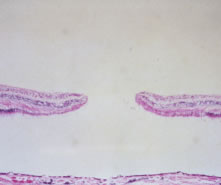

macular holes and cysts. Ophthalmology 1990;97:1045 18. Frangieh GT, Green WR, Engel HM. A histopathologic study of macular cysts

and holes. Retina 1981;1:311 19. Gass JD. Lamellar macular hole: A complication of cystoid macular edema